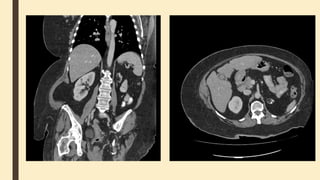

Computed tomography of kidneys,

ureters and bladder (CT KUB)

■ is a quick non-invasive technique for diagnosis of urolithiasis.

MRI

Renal cortex has slightly higher signal

than medulla on T1-weighted images.

On T2-weighted images, medulla has

slightly higher signal than renal cortex